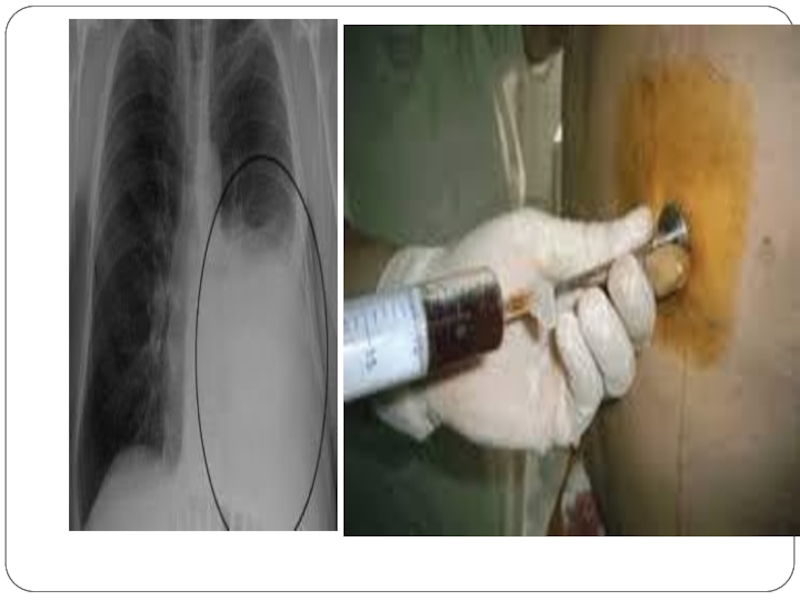

Слайд 50Іріңці плеврит (плевра эмпиемасы) диагнозын анықтауда рентгенологиялық, УД, КТ, бронхоскопия,

торакоскопия зерттеулерінің маңызы зор. Осы аталган зерттеу әдістерінің көмегімен плевра

қуысында сұйықтық бар екені анықталады. Оның көлемін анықтаған соң плевра қуысын инемен тесіп (пункция) сүйықтықтың мінездемесін анықтайды (серезды, іріңді қанаралас). Ірінді экссудат болса, оның антибиотиктерге сезімталдығын білу үшін, микробиологиялық зерттеу жүргізіледі.

Іріңці плеврит (плевра эмпиемасы) диагнозын анықтауда рентгенологиялық, УД, КТ, бронхоскопия, торакоскопия зерттеулерінің маңызы зор. Осы аталган зерттеу